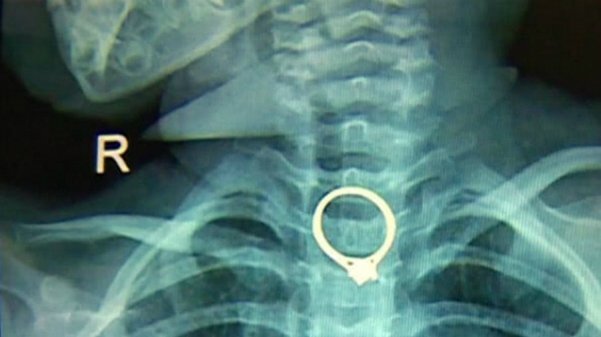

Ngủ quên, mẹ để con gái hóc nhẫn kim cương

Bé gái người Trung Quốc trong lúc chơi đùa vô tình nuốt chiếc nhẫn kim cương của mẹ.